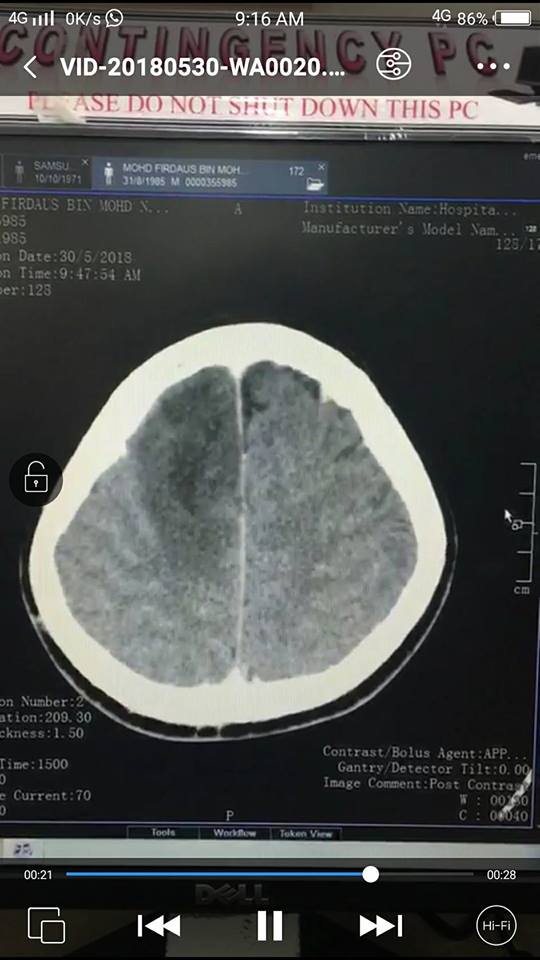

So, pendekkan cerita, di bawah ini adalah gambar CT Scan yang dibuat pada pagi Rabu 30 Mei. Gambar rajah kiri bersamaan otak kanan, yang kanan otak kiri. Selepas habis scan, aku pun baliklah dan tengah hari tadi dapat panggilan dari doktor Hospital Putrajaya (HPJ), suruh datang semula dan terus pergi ke Jabatan Kecemasan, jumpa doktor di bahagian semi kritikal.

Aku pun pelik dan tanya kenapa. Doktor kata, ada nampak ‘sesuatu’ di otak kanan aku bila masuk air contrast CT Scan.